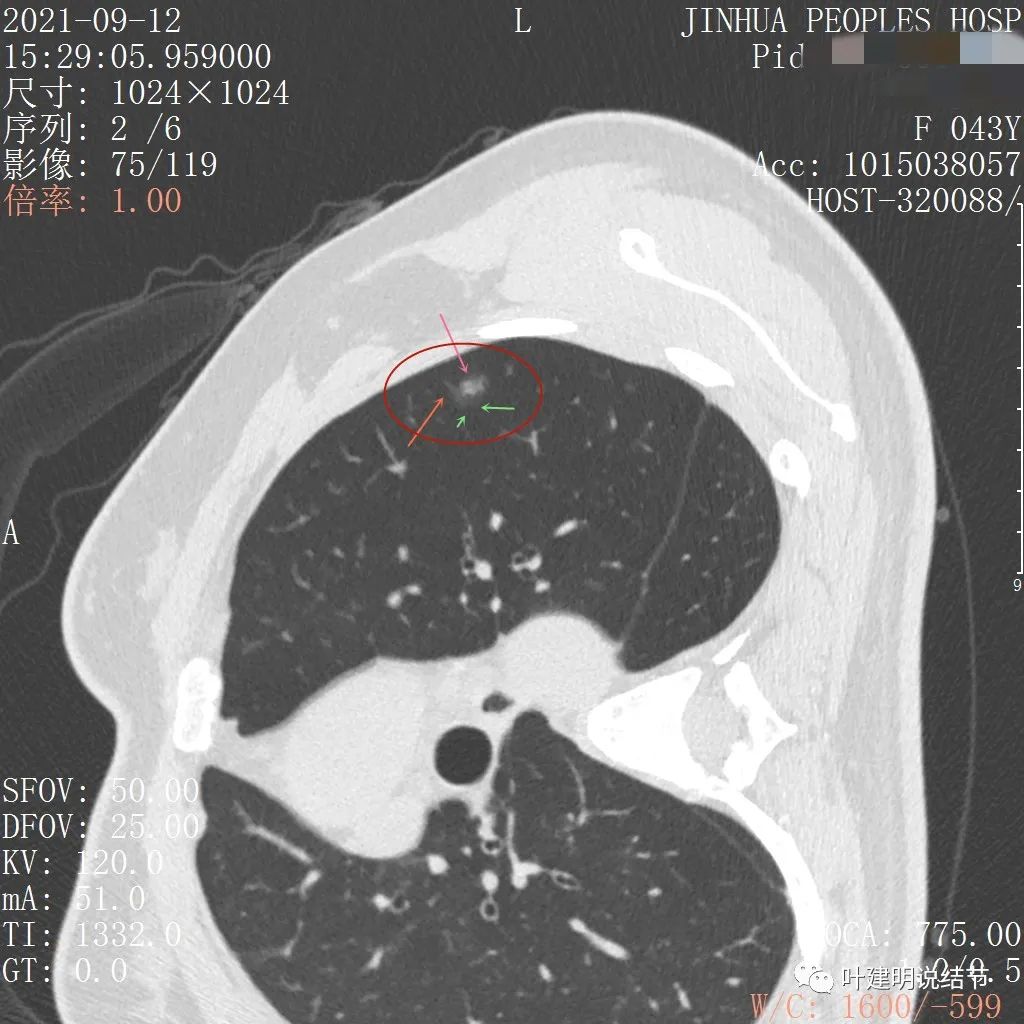

上图示病灶内部有高密度点状成分(粉色箭头所指)

同样示内部点状高密度,瘤肺边界清,密度显乱

上图显示混合磨玻璃结节,中间点状高密度区域,边上有微小血管征

上图示病灶边缘磨玻璃成分有的区域密度过低(绿色箭头),事后回头来看,磨玻璃部分的密度过低,不容易是浸润性腺癌,而更符合原位腺癌

上图示瘤肺边界处显模糊(砖色箭头),病灶内部仍是有偏高密度的点状成分